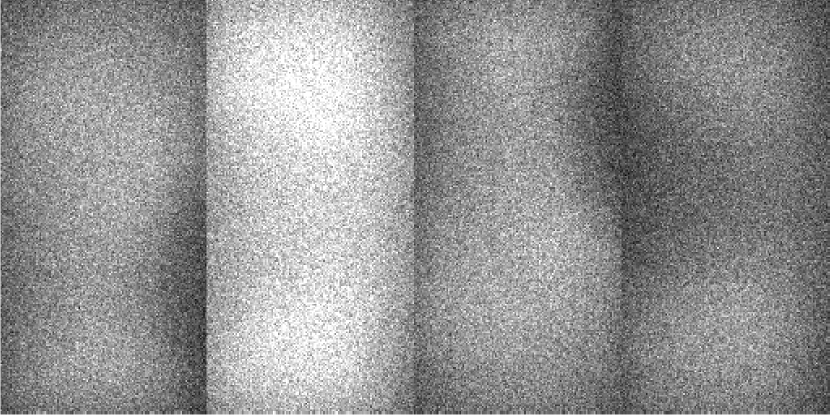

For illustrative purposes, select scatter estimates, along with the ground-truth are shown in Figure 4.